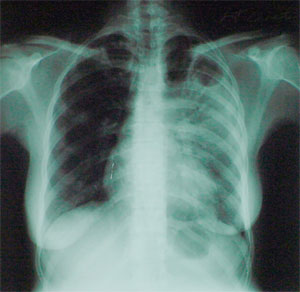

Рентгеновский снимок грудной клетки больного туберкулезом (фото с сайта www4.umdnj.edu)